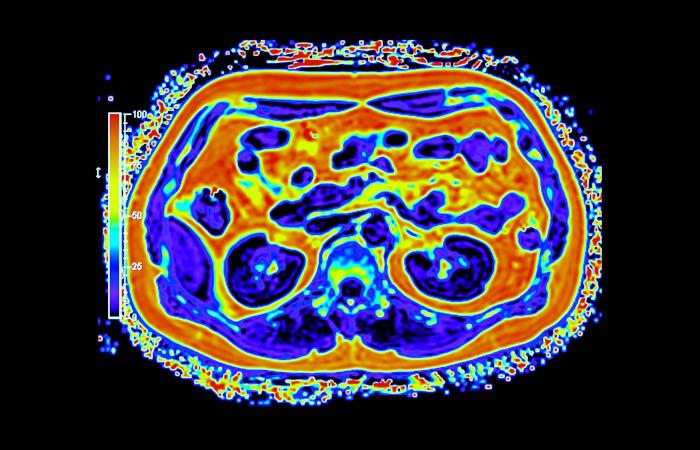

غالباً ما يُتناول تحوّل القطاع الصحي عبر محطات واضحة للعيان، مثل إنشاء مستشفيات جديدة، وإطلاق منصات رقمية، واعتماد أجهزة طبية متقدمة. غير أنّ جانباً أقل ظهوراً وأكثر حسماً يتمثل في بناء بنية تحتية تشخيصية قادرة على دعم الاكتشاف المبكر والطب الدقيق والرعاية الوقائية على نطاق وطني. ويقع التصوير الجزيئي، ولا سيما التقنيات الهجينة، مثل «PET - MRI» في صميم هذا التحول.

وعلى خلاف التصوير التقليدي، يجمع التصوير الجزيئي بين التفاصيل التشريحية والبيانات الوظيفية الآنية، ما يتيح للأطباء رؤية كيفية عمل الأنسجة لا مجرد شكلها. وفي مجالَي الأورام والأمراض العصبية، قد يُحدث هذا الفرق تحولاً في توقيت الاكتشاف أو في تعديل خطط العلاج أو في تجنّب إجراءات غير ضرورية. غير أن توسيع هذه القدرات عبر بلد واسع ومتنوّع جغرافياً يطرح تحديات تتجاوز كثيراً مجرد اقتناء الأجهزة.

أحرزت السعودية تقدماً تدريجياً في نشر أنظمة التصوير المتقدم، بما في ذلك «PET - CT» و«PET - MRI» داخل مراكز طبية كبرى. وبحسب الدكتور سامح الشيخ المدير العام لشركة التصوير الجزيئي والقطاع الطبي بوادي جدة، أثبتت هذه التقنيات قيمتها السريرية عبر الكشف عن انتشار سرطاني أو اضطرابات لم تُظهرها وسائل التصوير التقليدية، ما أتاح تعديل العلاج فوراً في عدد من الحالات.

لكن التركيز على المعدات وحدها قد يُبسّط المشكلة أكثر من اللازم؛ فالتصوير الجزيئي يعتمد على منظومة متكاملة تشمل إنتاج المستحضرات الصيدلانية الإشعاعية، وكوادر بشرية عالية التخصص، وإدارة آمنة للبيانات، ومسارات إحالة منسّقة.